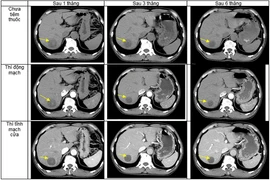

Nam bệnh nhân 60 tuổi ở Hà Nội đang được theo dõi tại Trung tâm Y học hạt nhân và ung bướu - Bệnh viện Bạch Mai cùng lúc mắc hai loại ung thư gồm ung thư hạ họng và ung thư biểu mô tế bào gan.